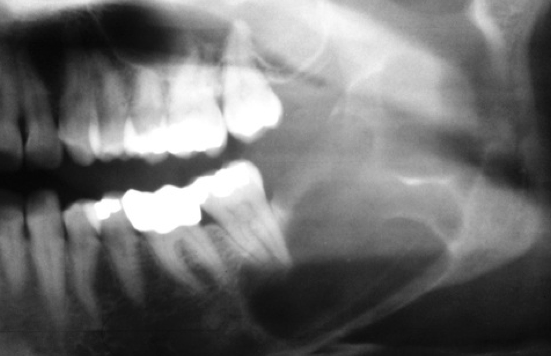

What is the likely Dx?

Odontogenic keratocyst. Note the multi lobule